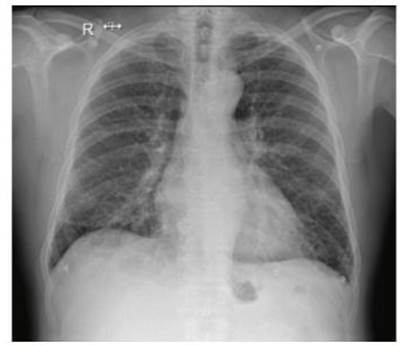

Ingresa en octubre de 2023 por historia de cuatro días de evolución dada por disnea de esfuerzo clase funcional II acompañada de disnea de decúbito, en apirexia. En el examen físico se encontraba lúcido, sin elementos de focalidad neurológica, normocoloreado, sin lesiones de piel. En lo cardiovascular, no se veía ni palpaba choque de punta, se encontraba normotenso, con un ritmo cardíaco regular de 60 cpm y un soplo sistodiastólico de intensidad 5/6 con máxima auscultación en el foco aórtico, irradiado a todo el precordio, con R2 abolido y frémito. No presentaba signos clínicos de insuficiencia cardíaca. El electrocardiograma evidenciaba alteraciones de la repolarización en cara lateral y la radiografía de tórax presentaba elementos de hipertensión venocapilar (Figura 1y2).

Figura 2 Radiografía de tórax enfoque de frente. Se evidencia leve redistribución de flujos a vértices sin otras alteraciones patológicas.